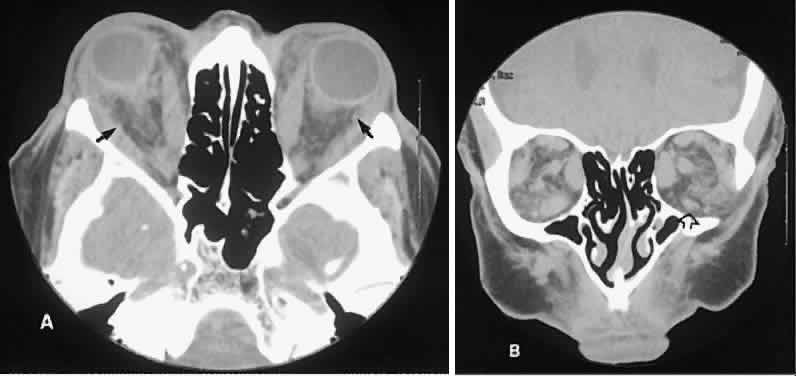

The CT evaluation of orbital myositis may show diffuse irregular enlargement of one or more EOMs; enlargement can be bilateral (Fig. 5). Incontradistinction to Graves' orbitopathy, involvement of the tendinous insertion and edema ofthe adjacent fat may be noted. Other conditions associated with EOM enlargement are listed in Table 2.31–33

Fig. 5. Axial views of orbital myositis. A. Note increased attenuation with enhancement of the thickened medial rectus and thickened scleral insertion. B. Thickening of the medial rectus muscle along the entire length of muscle is more evident.

Graves' orbitopathy probably represents the most frequent cause of proptosis and EOM enlargement. The CT findings are fairly stereotyped and typically display various degrees of EOM enlargement (Fig. 7). The inferior rectus muscle usually is affected earliest, followed by the medial rectus, superior rectus, and finally the lateral rectus muscle. Rootman and colleagues13 noted more frequent involvement of the superior rectus/levator and medial rectus muscles than what had been reported previously with Graves' orbitopathy. These muscles can be affected in isolation, with the exception of the lateral rectus. To the best of our knowledge, isolated lateral rectus enlargement has not been reported in Graves' orbitopathy and in our experience usually is associated with a sphenoid wing meningioma.

Fig. 7. Graves' orbitopathy with two variations. Axial (A) and coronal (B) views show symmetric fusiform enlargement of the extraocular muscles with tapered muscle insertions. Note the predominant enlargement of the inferior, medial, and superior rectus muscles with lesser involvement of the lateral rectus muscle, a frequent pattern of enlargement in Graves' orbitopathy. Axial (C) and coronal (D) views of Graves' orbitopathy with expansion of retrobulbar ground substance and relative sparing of the extraocular muscles.

CT evidence of Graves' orbitopathy tends to be bilateral. Approximately 86% of patients with unilateral clinical findings have bilateral CT findings in our experience, which is consistent with the experience of others.42

Morphologically, the EOM belly is enlarged, with a gradual tapering toward and sparing of the tendinous portion of the muscle. Tendon involvement is a typical feature of orbital myositis. Tendon involvement helps to differentiate this lesion from Graves' orbitopathy, although Rootman and Nugent43 have noted a rare patient with Graves' orbitopathy with this finding.